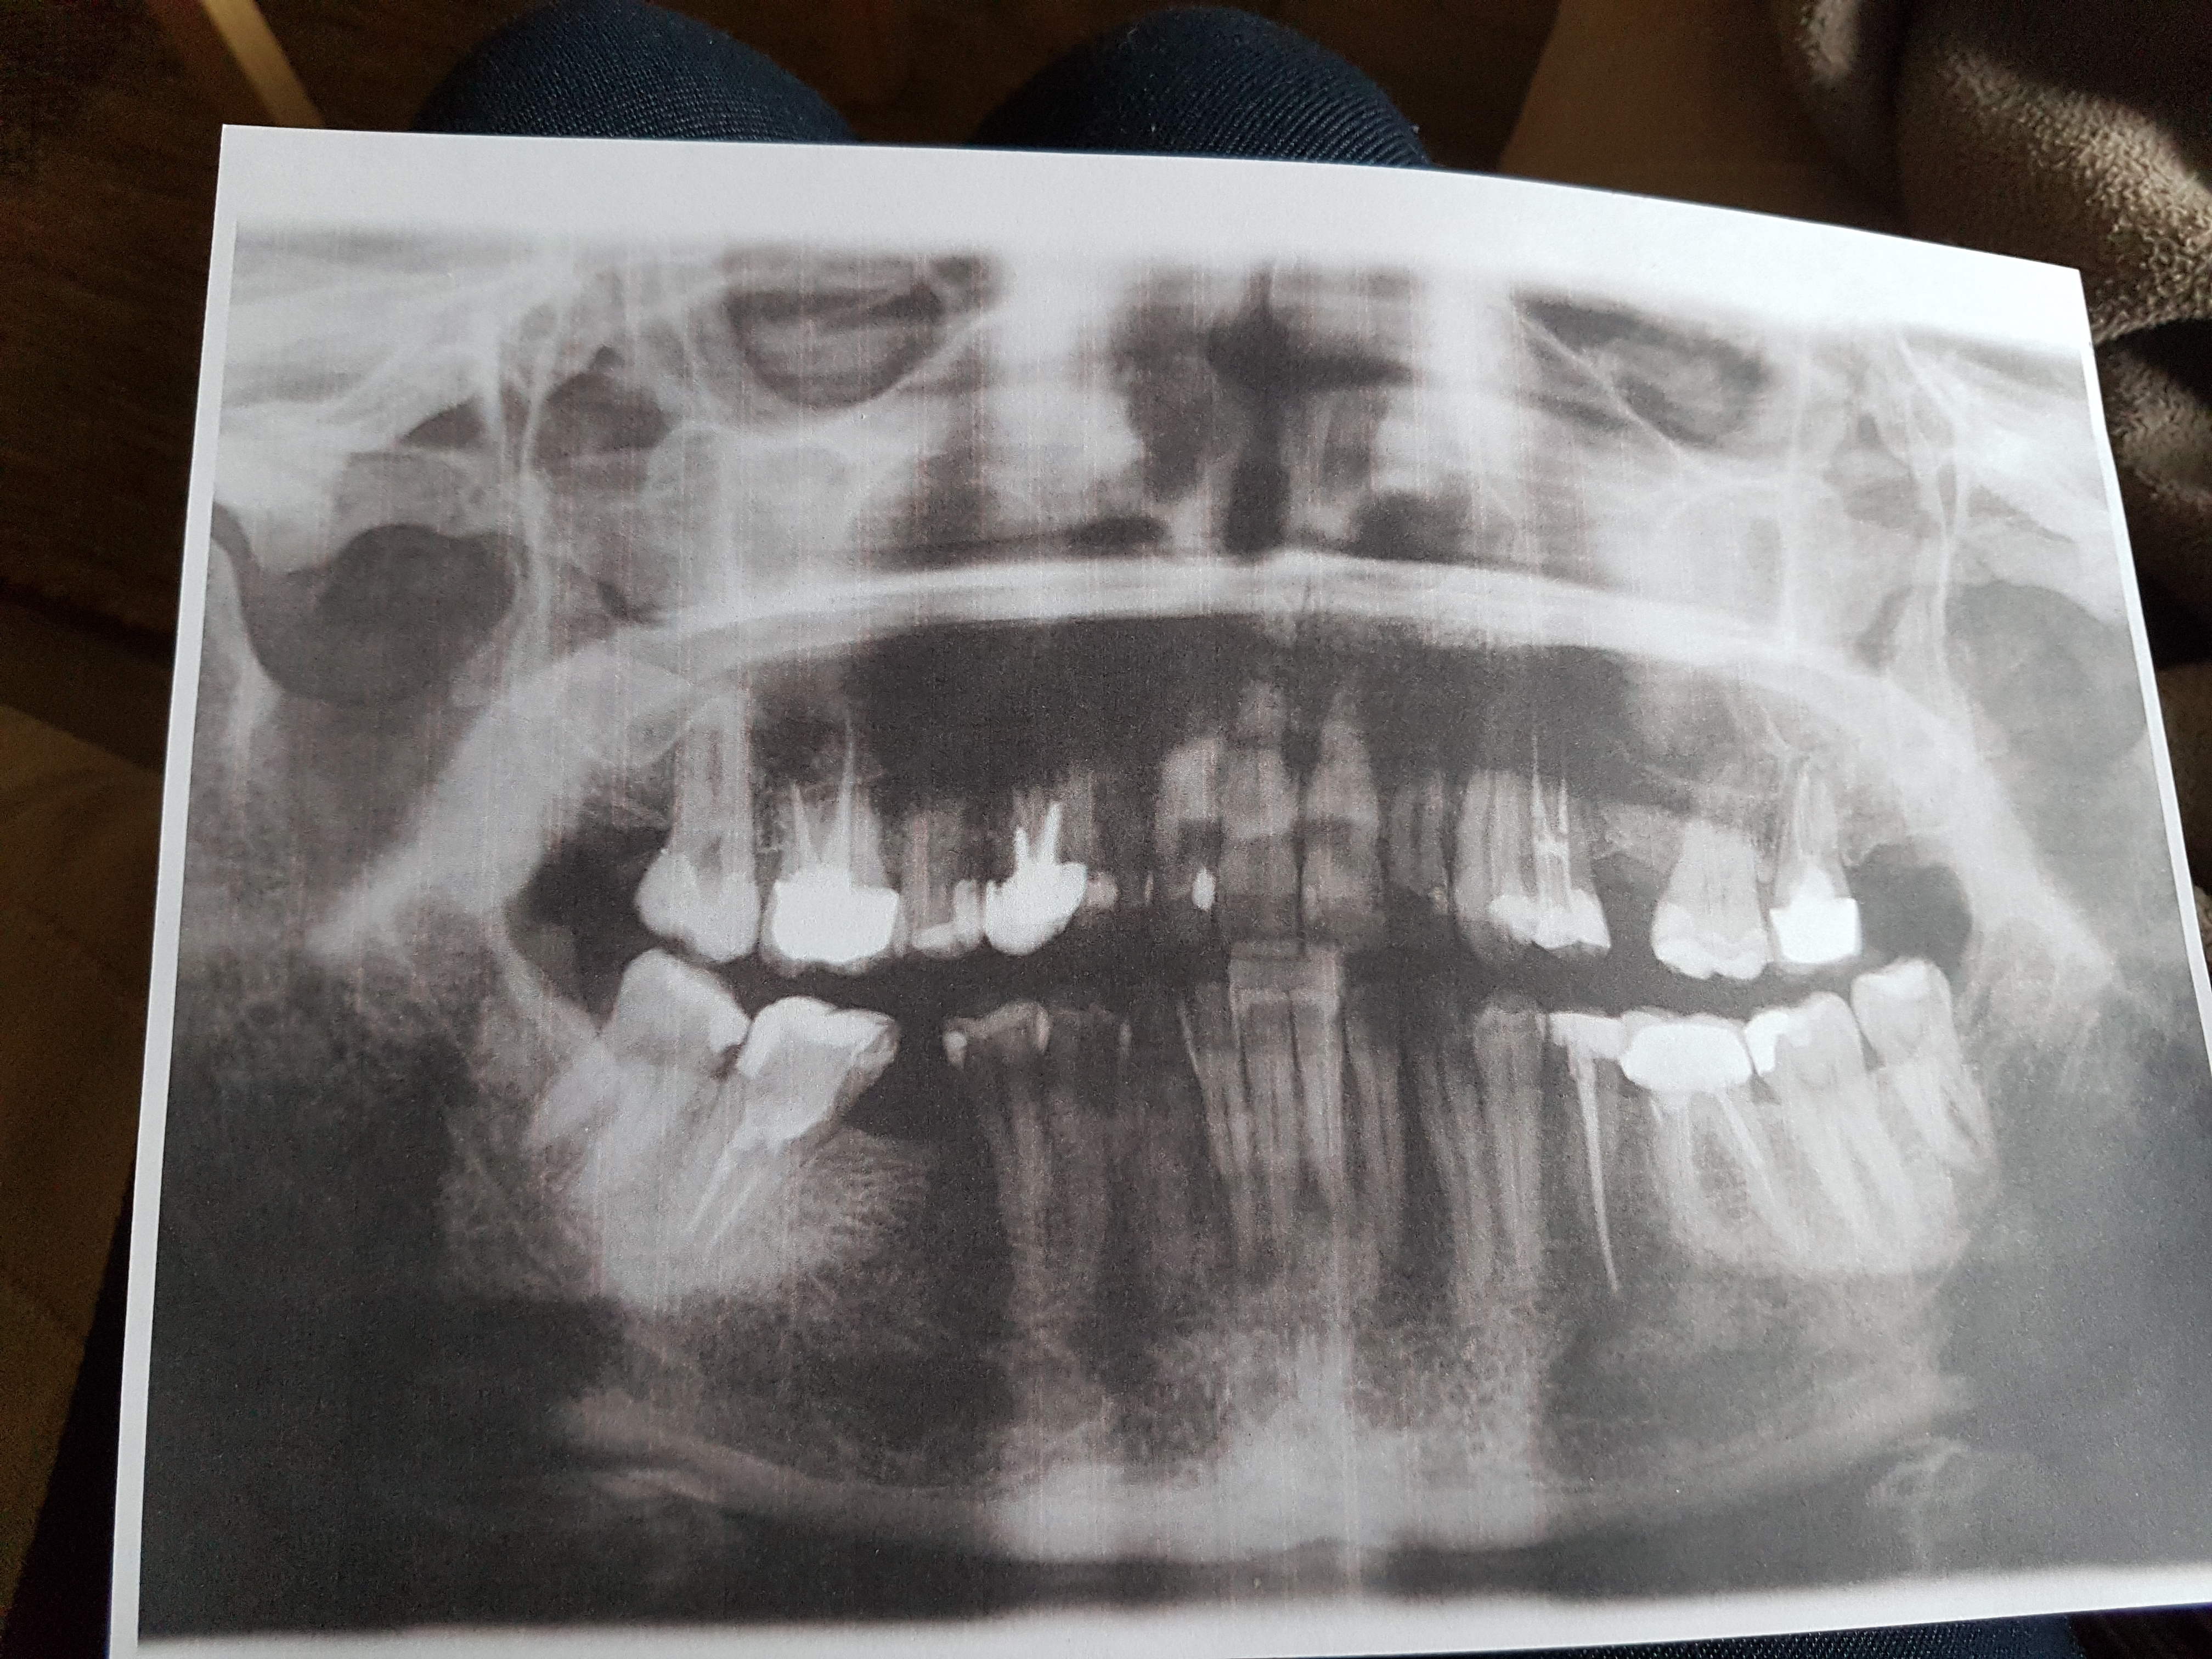

Технологические достижения: Planmeca и ОПТГ